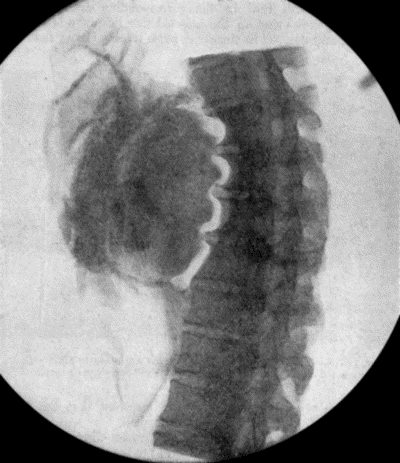

71.Radiogram of Aneurysm of Aorta 303

72.Sacculated Aneurysm of Abdominal Aorta 304

73.Radiogram of Innominate Aneurysm after Treatment by Moore-Corradi method 309